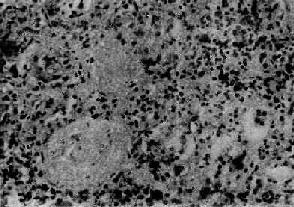

图12-7 弥漫性毛细血管内增生性肾小球肾炎

肾小球内细胞数量增多,系膜细胞和内皮细胞增生并有少量中性白细胞浸润,毛血管腔狭窄 ×320